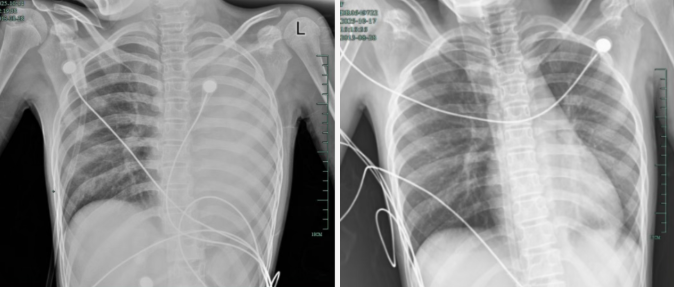

发热仅1天,肺全白了!这种病极度危险,千万别当普通感冒 2025-11-12

孩子感冒咳嗽看似常见,可12岁女孩笑笑(化名)的经历却让人感到后怕——仅发热1天,左肺就变成了“白肺”,呼吸急促到无法平躺,血氧饱和度勉强维持在90%左右,情况十分危急!治疗前后影响对比,左肺从“白肺”到正...